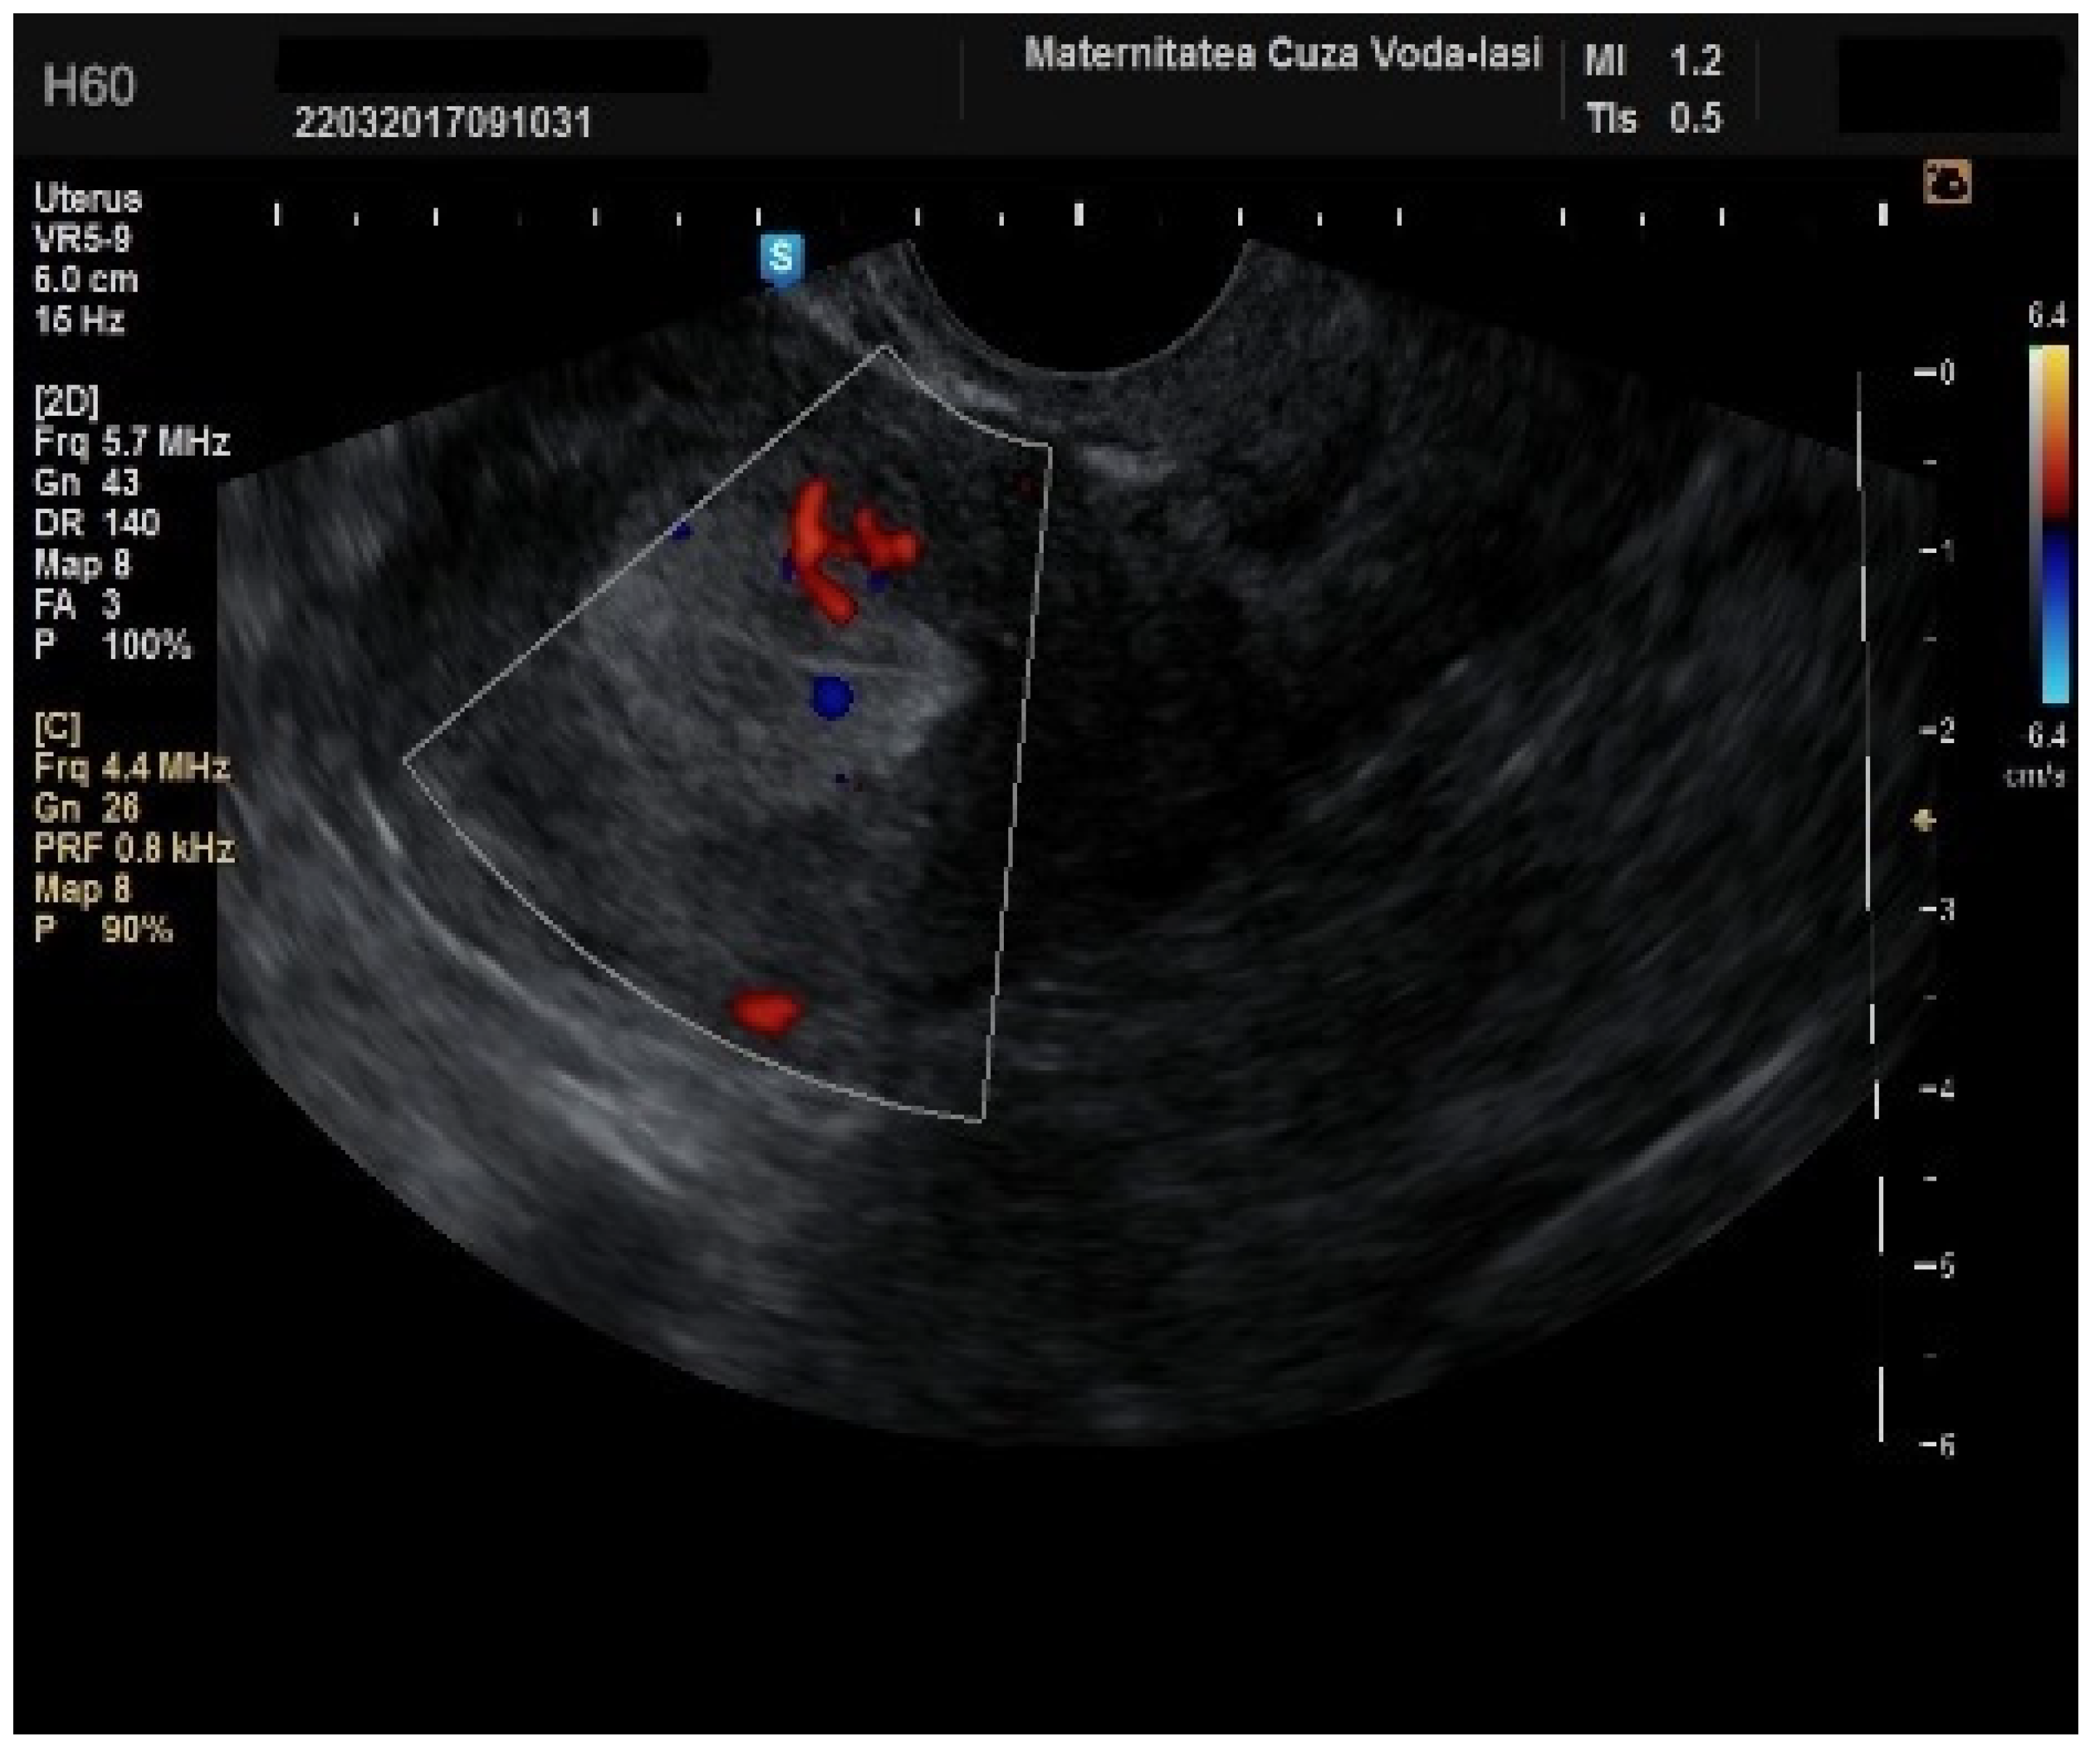

Regarding the color Doppler assessment, a vascular score of 1 usually excludes endometrial cancer, with a sensitivity of 87.5% and a specificity of 79% (Figure 8). This is due to the presence of a high number of newly formed vessels in malignant tumors (Figure 9).

Figure 9. Color Doppler vascular score 4 in endometrial cancer.